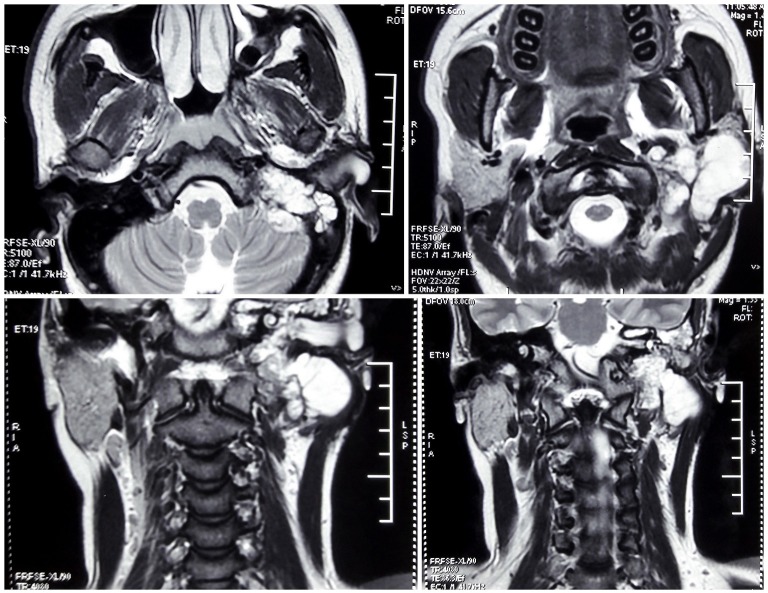

Pure tone audiogram showed a moderately severe conductive hearing loss (13 dB/68 dB) on the left side, and a normal hearing ear on the right side. Contrast-enhanced CT scan of parotid region displayed an isodense mass occupying left parotid, left external auditory canal (EAC) and left mastoid with erosion of anterior bony wall and floor of EAC as well as the mastoid air cells (figure 2). Contrast-enhanced MRI showed a mass, hypointense on T1, hyperintense on T2, with postcontrast enhancement, involving the left parotid region and left external auditory canal causing erosion of temporal bone and mastoid air cells with slight extradural extension to posterior cranial fossa (figure 3). With radiology favouring a malignant rather than benign lesion, an incisional biopsy was performed from the EAC mass which came out to be fibroepithelial polyp.

Figure 3.

Preoperative MRI films (top two—axial sections, bottom two—coronal sections).

Radiographically, chondrosarcomas present with bony scalloping, contrast enhancement or matrix calcification on CT. On MRI, there is typically T1 hypointensity, T2 hyperintensity and postcontrast enhancement9 as was seen in our case. However, there was a lack of the characteristic whorls or soap-bubble like appearance seen on T2-weighted and T1 postcontrast9 in our case. Histologically, these tumours demonstrate a hyaline cartilage neoplasm with mild to moderate cellularity, areas of myxoid change and focal host bone entrapment.9